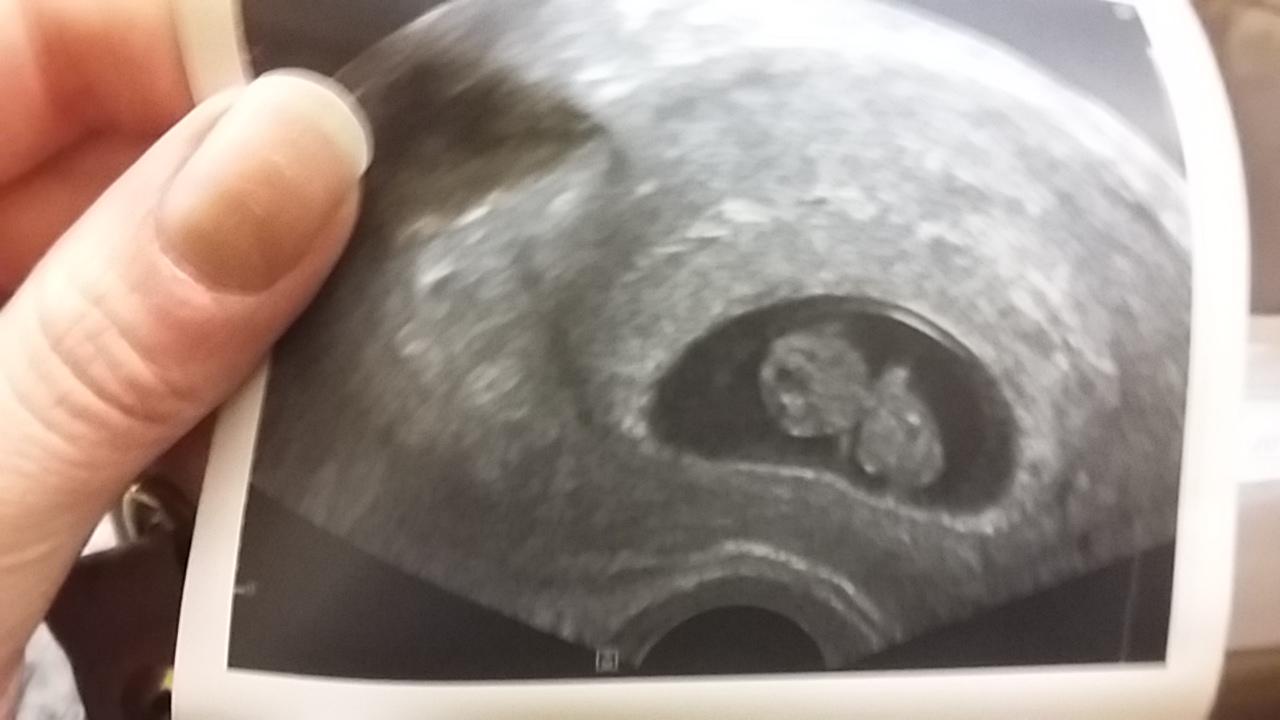

@arielka222 krásný mimčo malinký 🙂. 👏❤

@arielka222 jezis bobecek

@arielka222 to je tak krasny!!!!!!